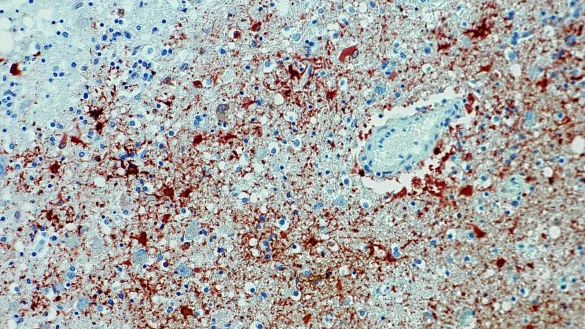

In Bayern ist eine sehr seltene Infektion mit dem Borna-Virus nachgewiesen worden. Betroffen sei ein Mensch im Landkreis Weißenburg-Gunzenhausen, teilte das Landratsamt in Weißenburg mit. Nähere Angaben zum Infizierten machte die Behörde nicht. Der Erreger löst eine Hirnentzündung aus, die in nahezu allen Fällen tödlich endet. Überlebende behalten meist schwerste Folgeschäden.

Der Erreger ist bei Tieren seit langem bekannt. Erst seit 2018 ist nachgewiesen, dass BoDV-1 auch auf den Menschen übertragbar ist und dabei meist tödliche Gehirnentzündungen verursacht. Das Robert Koch-Institut geht von zwei bis sechs Erkrankungen jährlich in Deutschland aus, Bayern ist dabei besonders betroffen.